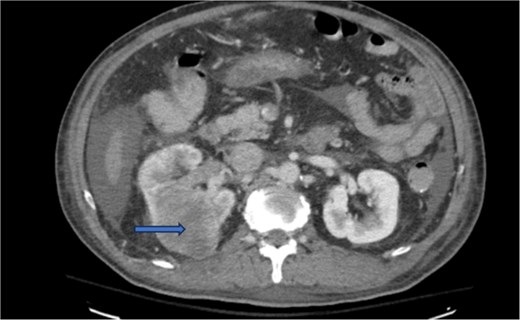

Diagnostic imaging began with a chest X-ray that indicated bilateral pleural effusions. An abdominal ultrasound detected a 4.6 × 4.2 × 4.3 cm echogenic lesion in the right hepatic lobe. Further imaging with a computed tomography (CT) scan of the chest, abdomen, and pelvis revealed a large mass originating from the posterior aspect of the right mid-kidney consistent with RCC (Fig. 1). The mass associated with thrombus extended into the renal sinus and collecting system, traveled along the right renal vein to the inferior vena cava (IVC), and projected into the right atrium (Figs 2 and 3). During hospitalization, bilateral lower extremity pain led to the diagnosis of bilateral deep vein thromboses via duplex venous ultrasound. Echocardiography showed normal left ventricular ejection fraction, impaired diastolic filling, mildly increased ventricular wall thickness, and an echogenic mass extending from the right atrium into the IVC consistent with the tumor thrombus.

CT chest abdomen and pelvis with contrast showing middle portion of right with tumor during venous phase venous phase.

CT chest abdomen and pelvis with contrast showing tumor thrombus is seen within the IVC extending over a long distance from the level of the renal vein cephalad into the right atrium.

CT chest abdomen and pelvis with contrast showing inferior extension to the level of the distal margin of the IVC.